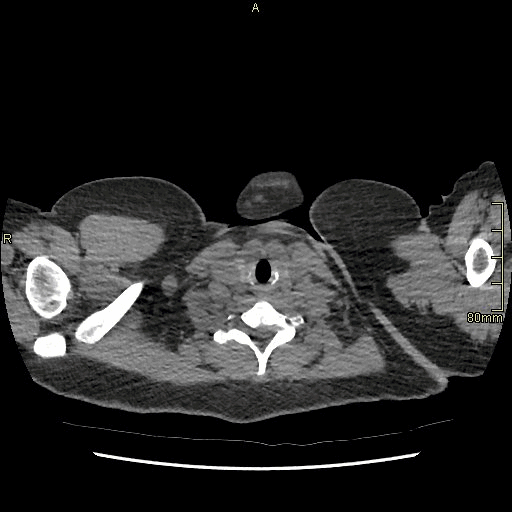

Example below is a General Chest/Abdo/Pelvis without contrast. Bony reconstructions are available depending on clinical question and differential diagnosis

Chest/Abdo/Pelvis (Coronal)

Lung (Coronal)